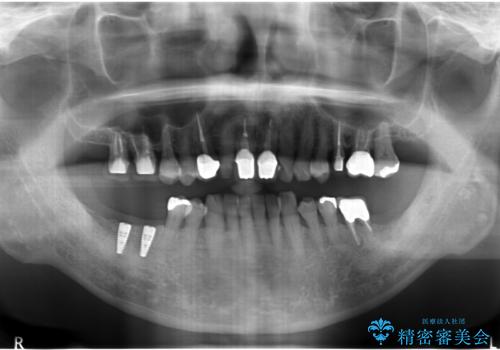

- 右下の奥歯が割れてしまい、抜歯を行いました。

ブリッジにできない位置であったため、インプラントでかめるようにしました。

また、向かい合う上の歯が挺出(伸び出してしまうこと)しており、インプラントを入れることが難しかったため、長さを短くかぶせ治しました。

また、上顎前歯以外の根の治療のやり直しを行いました。

左下に関しては、経過観察を行い、歯が割れたりした場合にインプラントを考えることになりました。